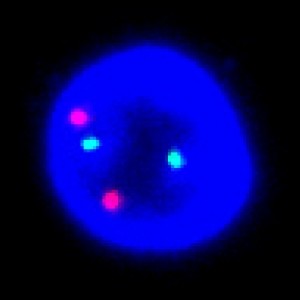

Close-up of a group of nuclei including gene probes.

To determine the HER2/CEN-17 ratio, the total number of HER2 signals (Red) and the number of CEN-17 (Green) signals in the same 20 nuclei are identified. The total number of HER2 signals is then divided by the number of CEN-17 signals. Ratios above 2 are classified as amplified whereas ratios below 2 are classified un-amplified. Caution should be taken when intepreting on results near the cut-off (1.8 – 2.2). The operator only needs to define an overall region of interest.